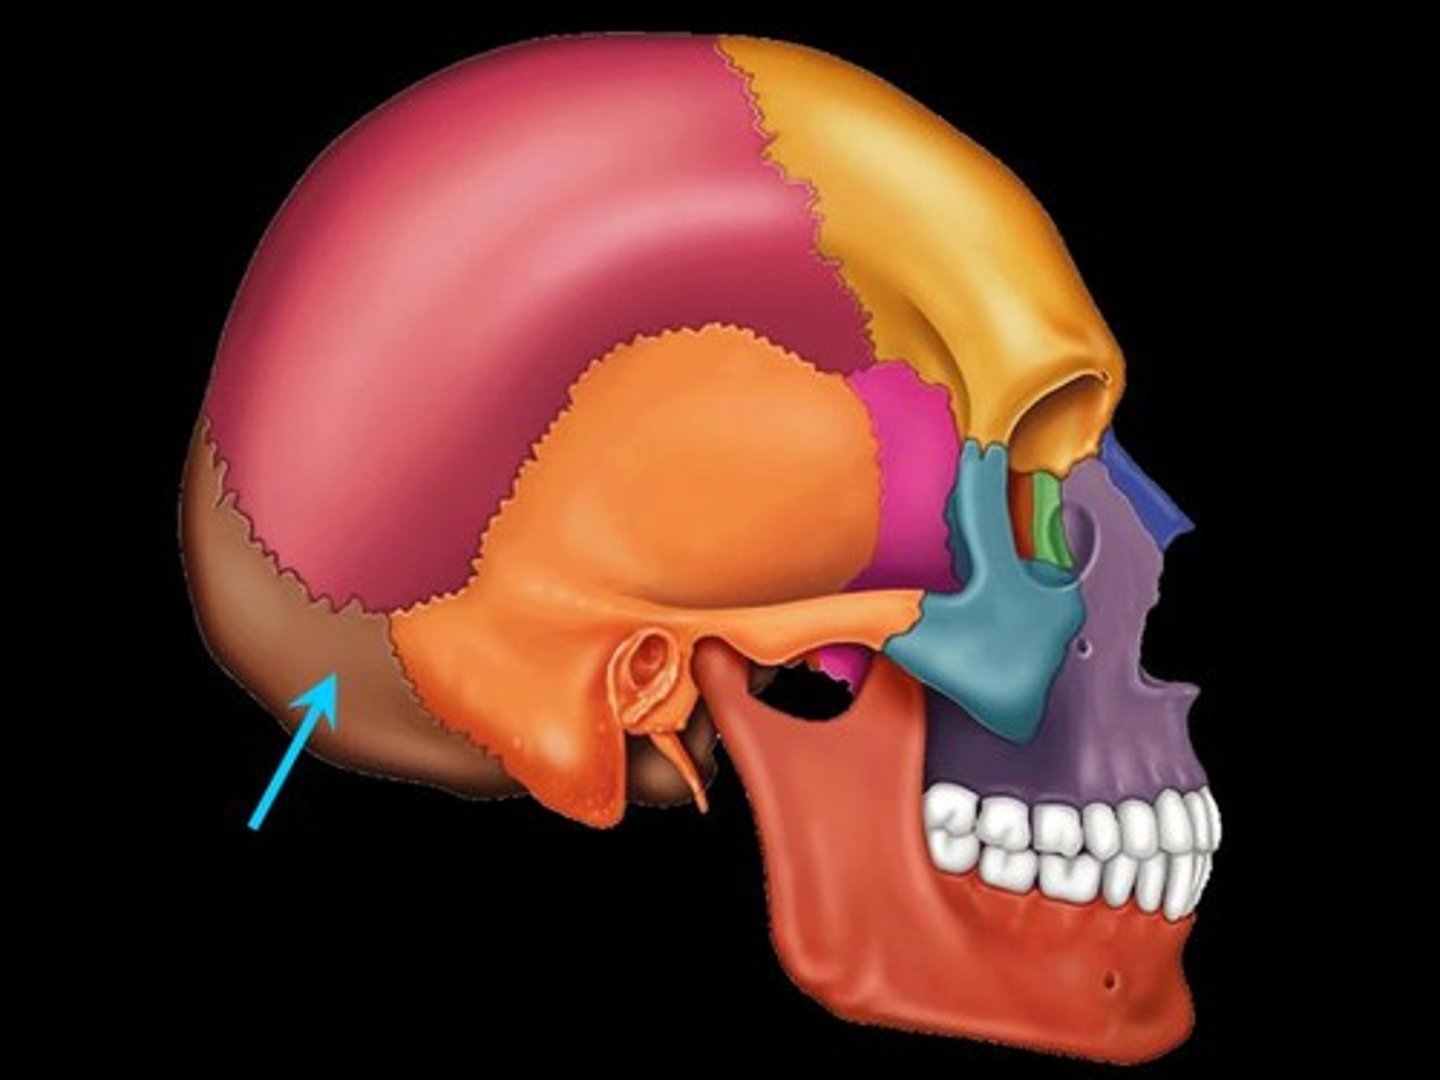

Temporal Bones

The lateral bones on each side of the cranium; the temples

Zygomatic Process/Arch

Extends out, touches cheek (bridge-like)

Mastoid Process

Round projection on the temporal bone behind the ear

Styloid Process

Pole-like process extending downward from the temporal bone on each side of the skull